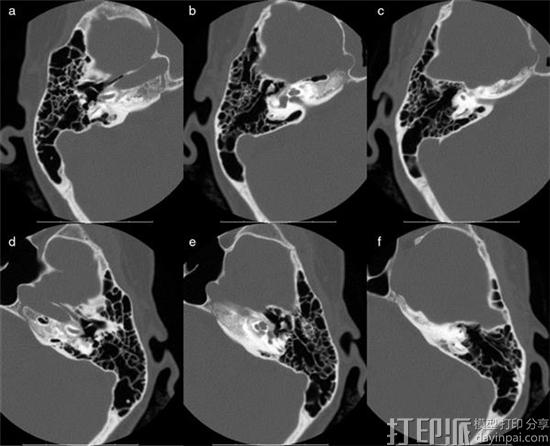

该团队使用CT扫描仪从三具尸体中获取中耳骨骼的成像数据。用仿造的创新套件软件设计定制假体,然后用树脂材料通过Formlabs Form 2 SLA 3D打印机打印出来。最后由4名外科医生成功将假体模型与正确的中耳部分相匹配(四名外科医生对小骨假体设计毫不知情)。据Hirsch说,这种随机发生的概率大约是1/296,这项研究突出了3D打印的核心优势-能够非常准确地将组织结构空间关系复制到亚毫米级。

3D打印的假体植入物